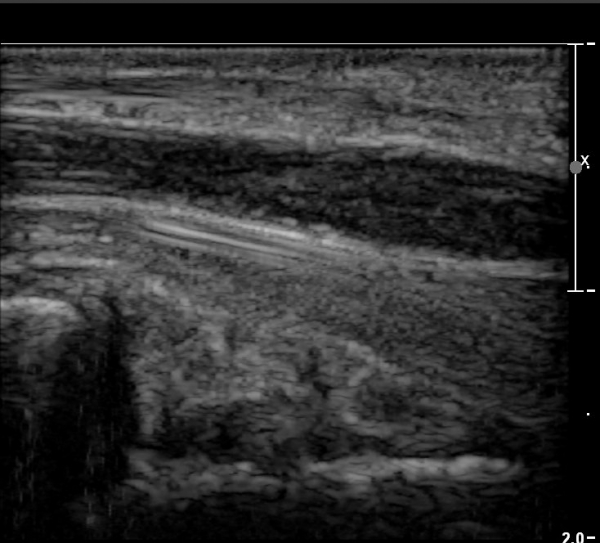

ÀÌ·± ¸ð½ÀÀº ¼Õ¸ñÀÇ ¿ù»ó°ñ ºÎÀ§(»çÁø 3, 4)¸¦ Áö³ª ¼ö±Ù°ü ±ÙÀ§ºÎ ±îÁö À̾îÁü(»çÁø 5).

ÇÏŰ½ºÆ½(°íÁÖÆÄ) ŽÃËÀÚ¸¦·Î °üÂûµÈ ¸ð½À¿¡¼­ Á¤Áß½Å°æ ºÎºÐ ½Å°æ´Ù¹ßÀÇ Àú¿¡ÄÚ

º¯È­°¡ ¶Ñ·ÈÇÔ(»çÁø 6, 7).

Á¤Á߽Űæ Á¾´Ü¸é°Ë»ç¿¡¼­µµ ¼Õ¸ñ ¸»´ÜºÎ¿¡¼­ ¼ö±Ù°ü ±ÙÀ§ºÎ±îÁö À̾îÁø Àú¿¡ÄÚ

Á¾¾çÀÌ °üÂûµÊ(»çÁø 8, 9, 10, 11).